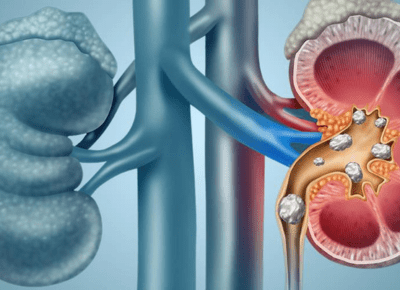

Kidney stones are hard deposits formed from minerals and salts that build up in the kidneys. They vary in size—from as small as a grain of sand to as large as a golf ball—and may cause severe pain as they pass through the urinary tract. Common causes include dehydration, certain diets, obesity, medical conditions, and family history.

Treatment depends on the size, type, and location of the stone, as well as the severity of symptoms. Below are the most common options:

This non-invasive procedure uses shock waves to break stones into smaller pieces, making them easier to pass. ESWL is one of the most common medical procedures for Kidney Stone Treatment when stones are too large to pass naturally.

For stones lodged in the urinary tract, doctors may use a thin scope to locate and remove them or break them apart using lasers. This approach is effective for medium-sized stones that are resistant to other treatments.

5. Percutaneous Nephrolithotomy